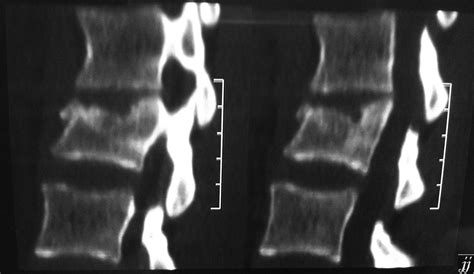

The clinical significance of this fracture type lies in its potential to cause significant pain and instability in the spine. Patients might experience localized back pain, muscle spasms, and even neurological symptoms if the fracture impinges on the spinal cord or nerve roots. Diagnosing a vertebral endplate impaction fracture typically involves imaging techniques such as X-rays, CT scans, or MRI. MRI, in particular, is excellent for visualizing the soft tissues and detecting subtle fractures or bone bruises that might not be apparent on X-rays. Treatment options vary depending on the severity of the fracture and the patient’s overall health. Conservative measures such as pain management, physical therapy, and bracing are often the first line of defense. In more severe cases, surgical intervention might be necessary to stabilize the spine and prevent further complications. Understanding the nature of this fracture is paramount for healthcare providers to select the most appropriate ICD code, ensuring accurate billing and proper documentation of the patient’s condition.